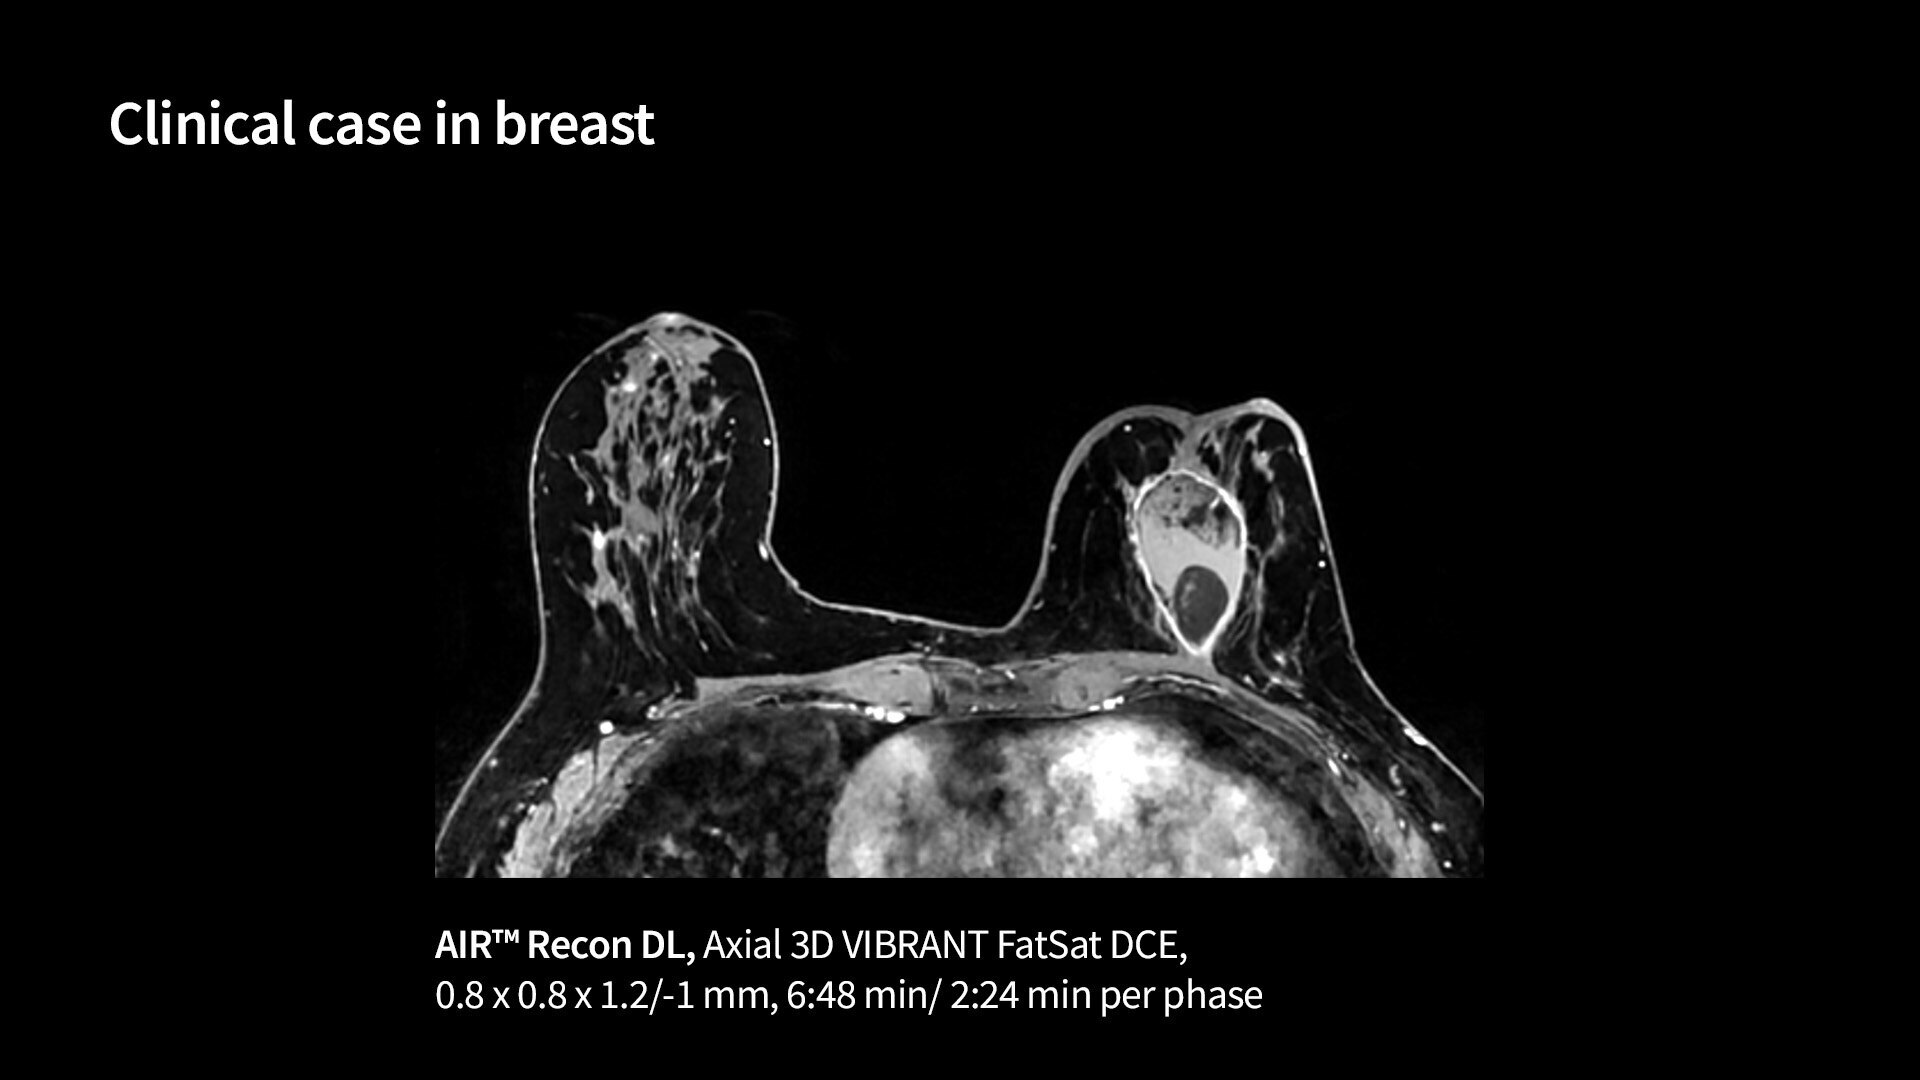

<p>VIBRANT (compatible with AIR™ Recon DL) &amp; VIBRANT Flex</p>

Read case study ico-caret-right